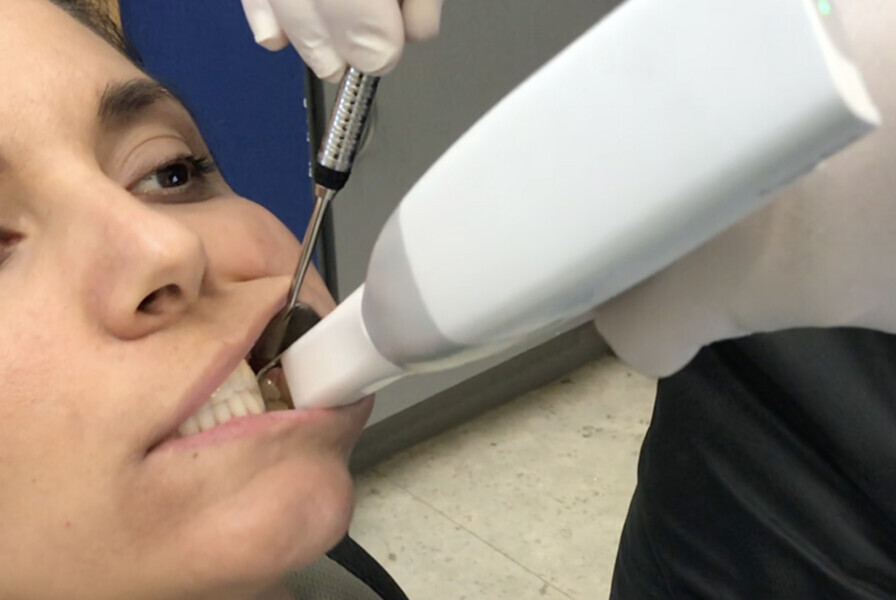

Fig. 24: Centric relation recording using an intra-oral scanner while the mandible is stabilised by a leaf gauge at the desired vertical dimension of occlusion.